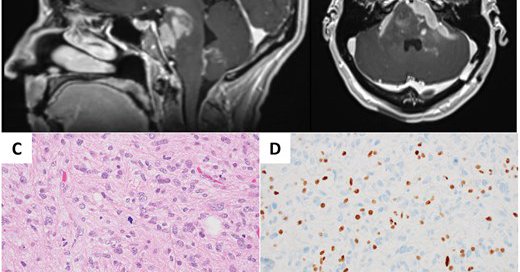

Posterior fossa 4th ventricular brain mass in a young patient, what molecular alterations are likely detected in this lesion? πŸ€” #pedipath #neuropath #pathology

Mass sitting next to the cerebellum. Diagnosis? #pathology #neuropath #pathtwitter

Methylation Case of the Week: 37 year old female patient with a pineal region tumor. Please Take your time Pondering the gene and Region of the case for the diagnosis. bonus question: can you PreTENd to guess the mutant gene in this case? #Neuropath #Pathology #Pathtwitter